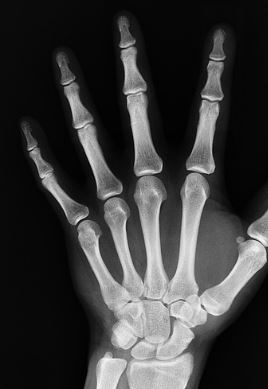

뼈가 튼튼하면 신체에 활력이 도는데, 골밀도가 떨어지면 조그마한 충격에도 골절을 입을 수 있어 진짜 조심해야 합니다. 특히 나이가 들수록 골밀도가 약해지는데, 남자보다 여자가 더 골다공증에 잘 걸린다고 하더라고요.

골다공증은 뼈가 약해져서 깨지기 쉽고 부러지기 쉬운 상태를 말합니다. 골다공증 관리에는 뼈를 강화하기 위한 영양소가 풍부한 식품을 꾸준히 챙겨 먹으면 좋은데요, 오늘은 이번에는 골다공증에 좋은 음식 10가지와 그 이유에 대해서 알아보겠습니다.